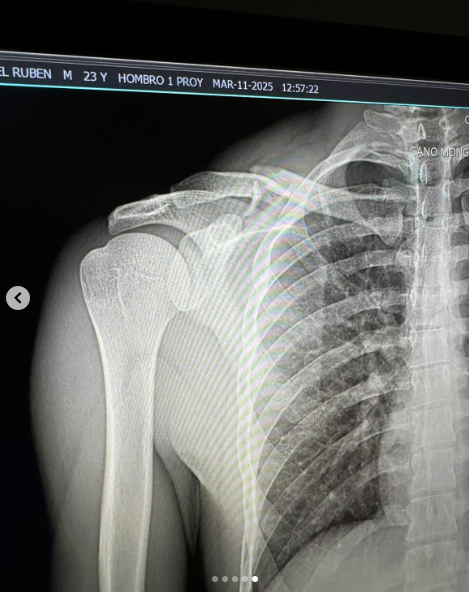

A travÃs de sus redes sociales, el intÃrprete de âPRCâ y âPresidenteâ compartià una serie de imÃgenes de su proceso de recuperaciÃn. En una de las fotos, muestra la radiografÃa de su clavÃcula rota y escribià con humor: âClavÃcula salià del chatâ, refiriÃndose a lo sucedido durante su accidentado vuelo por los aires mientras practicaba motocross con su amigo y corredor estadounidense Kaed Kniffing, a quien bromeà diciendo que al menos lo vencià en la competencia.

A pesar de la gravedad de la lesiÃn, que requirià cirugÃa, Natanael Cano se mostrà optimista y en buen Ãnimo. En sus historias de Instagram, agradecià a sus fans por su preocupaciÃn y asegurà que se encuentra en proceso de recuperaciÃn: âLos amo. Un pequeÃo accidente fuera de mi alcanceâ.